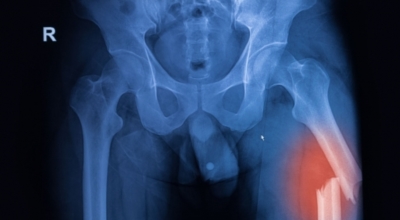

각별히 젊은 남성분들에게 잘 발생하며 엉덩이와 골반 주위에 뻐근한 통증이 동반되며 정상적인 보행이 되지 않고 절뚝거리는 증상이 나타난다면 대퇴골두 무혈성 괴사일 가능성이 있습니다. 이 증상은 괴사 부위의 골절이 발생되어 고관절 훼손으로 이어지면 생기는 증상으로 아직까지 정확한 원인은 규명하기 힘드나 과음이나 고지혈증, 스테로이드 과남용이 영향을 줄 수 있답니다.

그러나 비수술 치료법으로 개선시키는 것이 어려운 경우 수술적 방법이 고려되어요. 고관절 통증을 조기에 치료하면 약물치료 외에 물리치료로 약 50% 정도 큰 효과를 볼 수 있답니다. 게다가, 보통 고관절 증상 관리에 보탬이 되는 요가, 수영, 스트레칭은 고관절 예방과 치료에 보탬이 돼요.